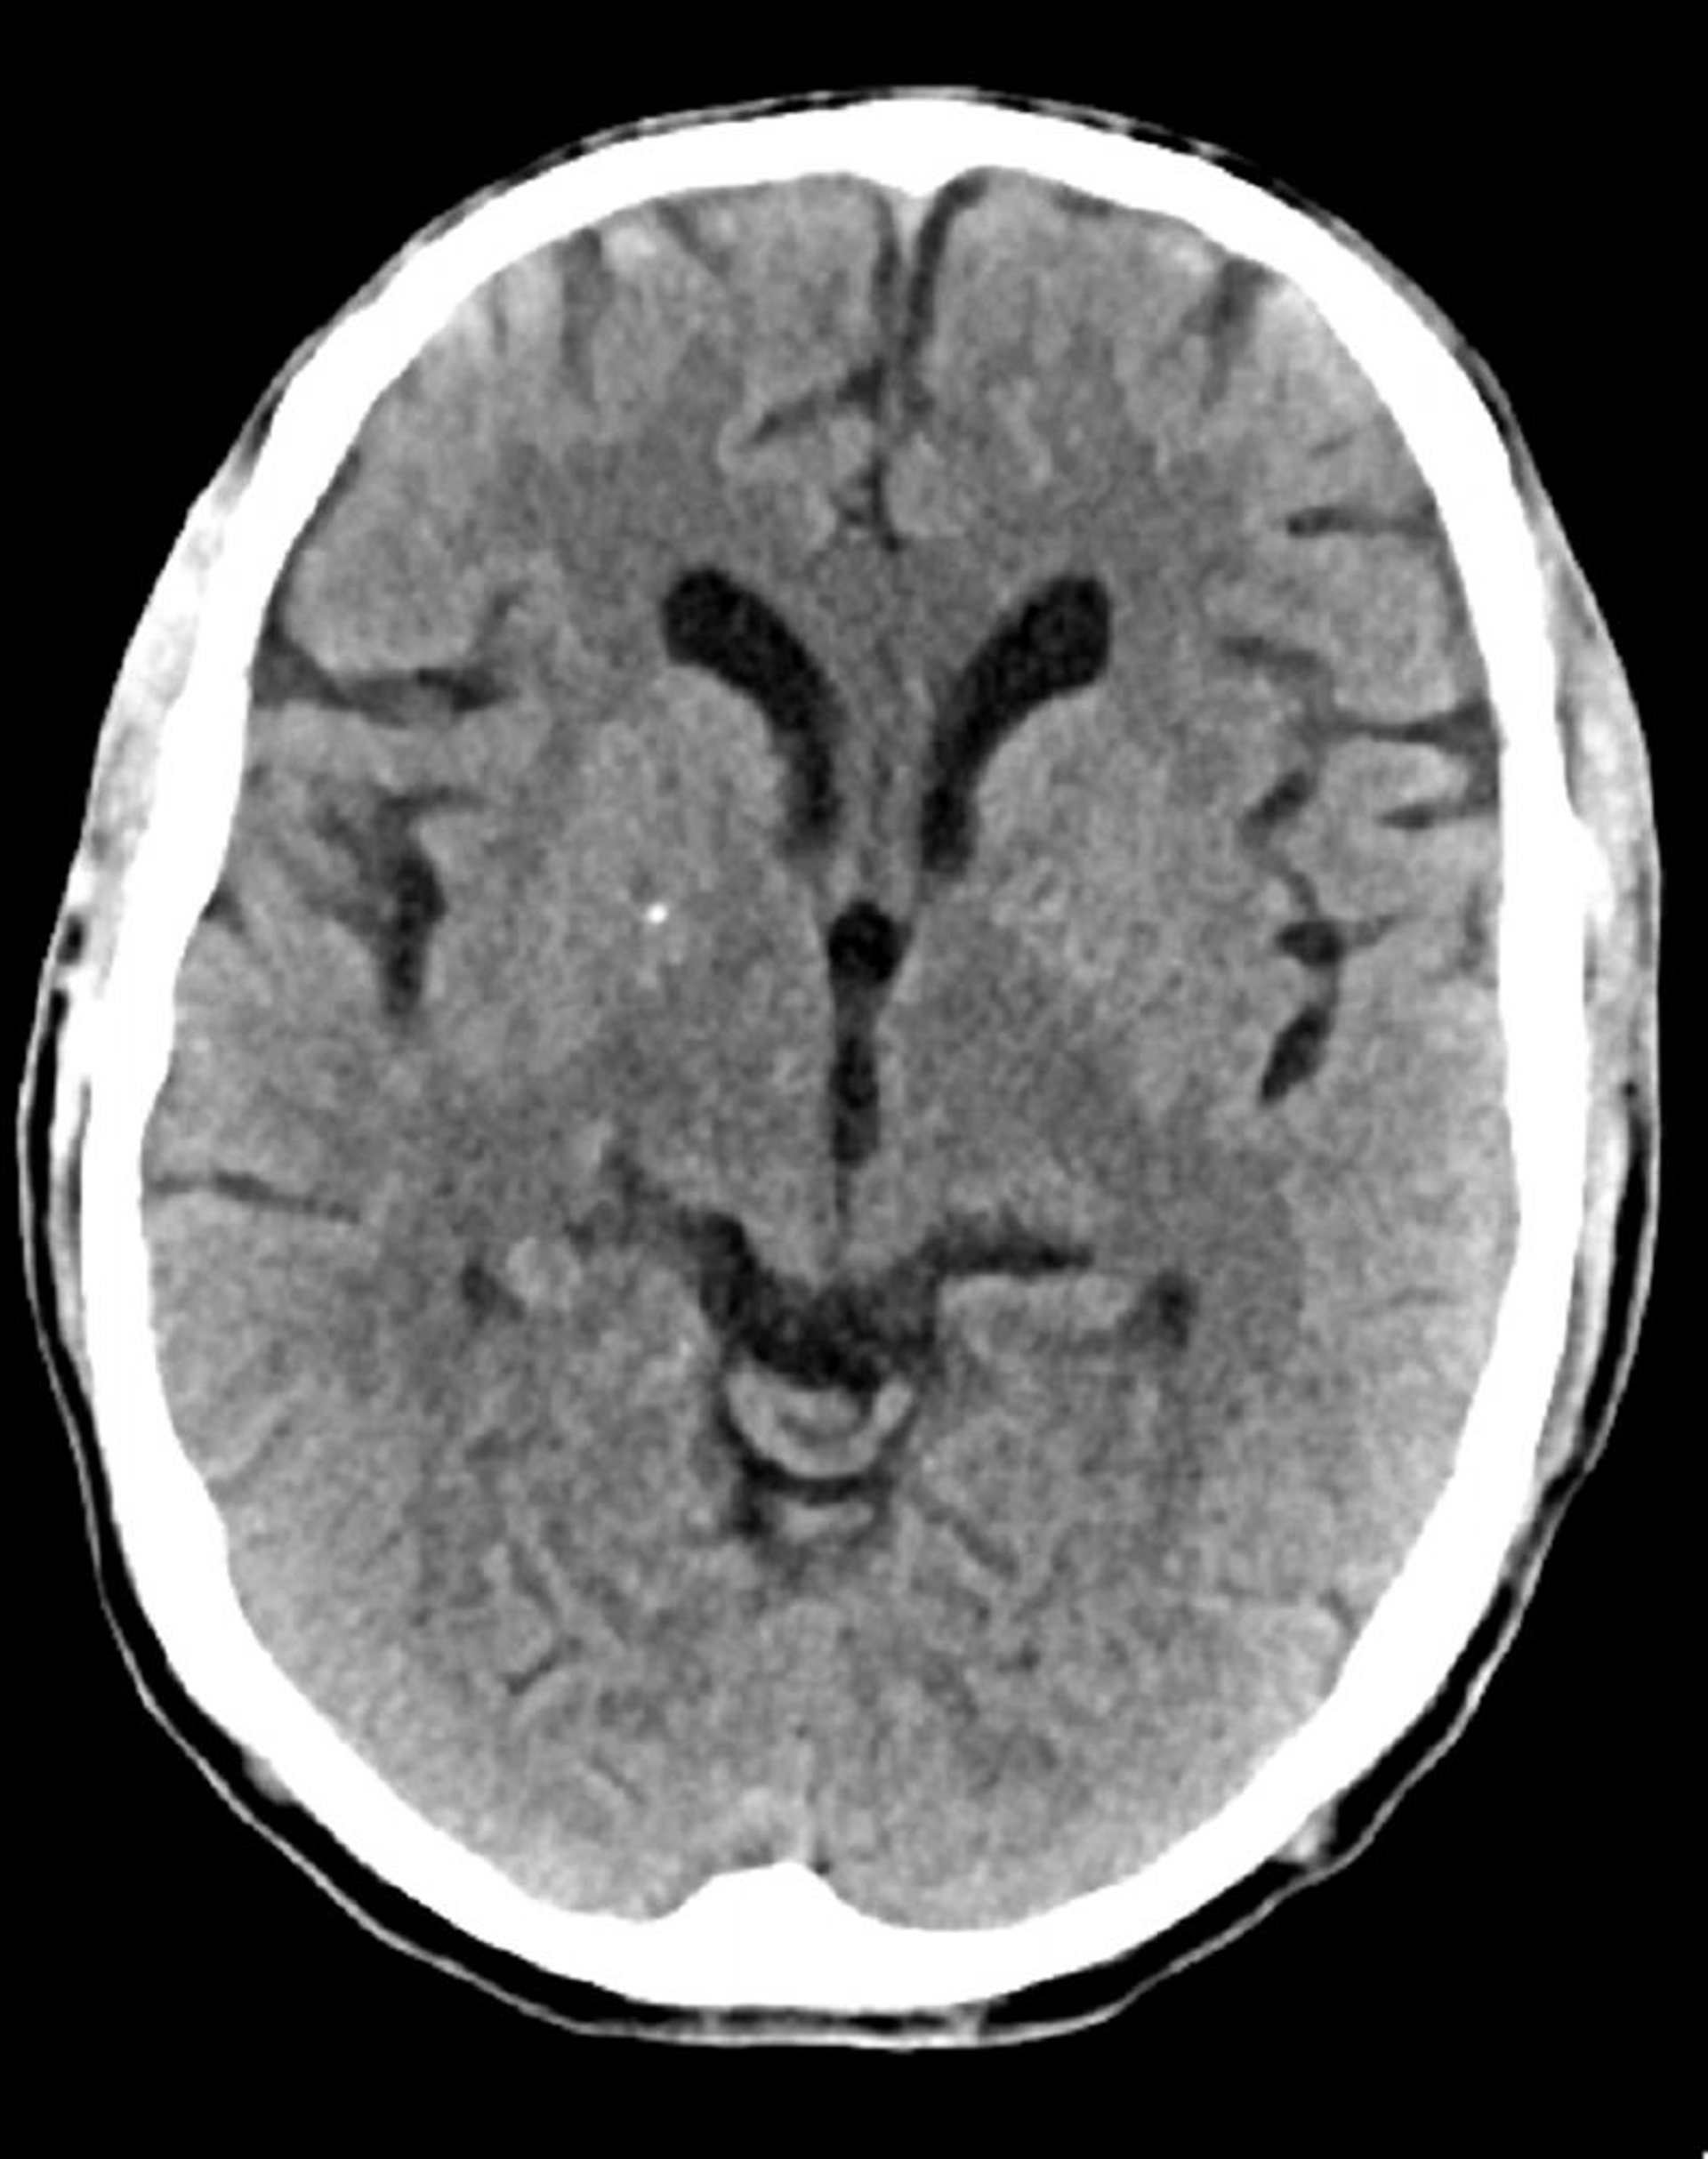

Tomodensitométrie normale de la tête (adulte, 74 ans) – Diapositive 6

Cette image est une TDM normale de la tête d'un adulte âgé de 74 ans. Par rapport à la TDM normale de la tête d'un patient de 30 ans, les ventricules et les sillons sont plus grands. Ces signes sont normaux dans ce groupe d'âge.